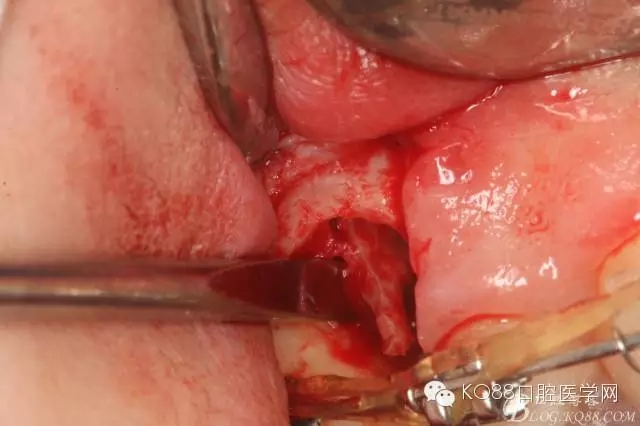

圖11.仔細(xì)考慮之后,在14頰側(cè)做垂直切口,切口長度僅達膜齦聯(lián)合處,做小切口。

圖12. 做垂直切口+齦溝內(nèi)切口,形成角形瓣,暴露出15根面。